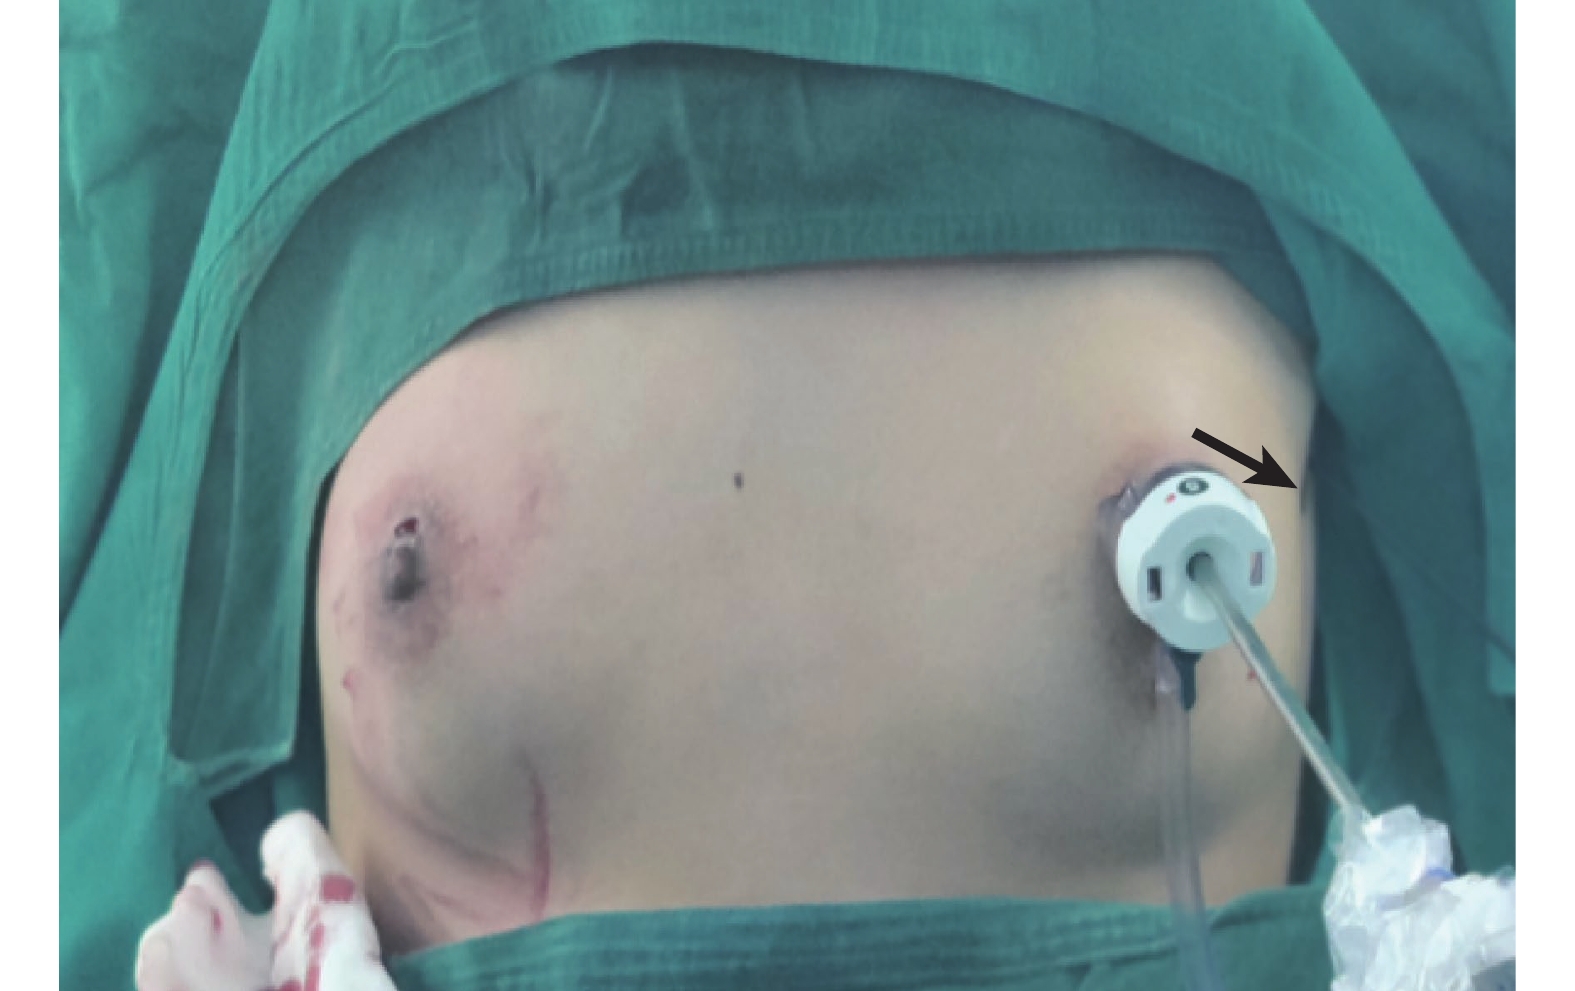

觀察組行無管化條件下3 mm胸腔鏡聯合針型電凝鉤胸交感神經離斷術。麻醉誘導:舒芬太尼0.5~0.6 μg/kg、依托咪酯0.2~0.3 mg/kg、順苯磺酸阿曲庫銨 0.15~0.3 mg/kg;術中麻醉維持:瑞芬太尼0.2~0.6 μg/(kg·min)、丙泊酚4~12 mg/(kg·h)持續靜脈泵入。麻醉誘導成功后使用喉罩輔助呼吸。患者取仰臥半坐位,雙臂外展90°。常規消毒鋪巾。選取右側乳暈處作為鏡孔,置入Trocar及3 mm胸腔鏡(圖1),使用氣腹機使肺組織萎陷,探查胸腔,反復確認并定位T3交感神經干。待肺組織萎陷滿意后于右側腋前線第3或第5肋間使用針型電凝穿刺套管進行穿刺(圖2),穿刺成功后使用其中針型電凝鉤電灼離斷T3交感神經干,并沿肋骨延伸2~3 cm的長度,以徹底燒灼潛在的旁路分支(Kuntz束及側束)術中見到交感神經干徹底離斷、兩側斷端距離3~5 mm、兩側斷端神經纖維向后攣縮即可,術畢充分止血。撤出穿刺套管后關閉氣腹機,使用氣腹管排出胸腔殘氣,使肺完全復張,之后緩慢移出胸腔鏡及Trocar。清點敷料器械無誤后縫合切口或噴灑醫用生物膠,穿刺套管穿刺處以無菌敷貼覆蓋。同樣的方法切斷左側交感神經干。

a:觀察組手術切口(鏡孔經乳暈,箭頭所示為針型電凝鉤穿刺處);b:對照組手術切口(鏡孔經乳暈,箭頭所示為操作孔切口)